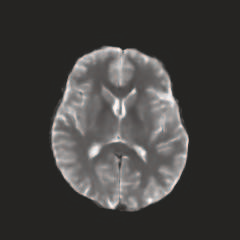

Multi-modal medical image completion has been extensively applied to alleviate the missing modality issue in a wealth of multi-modal diagnostic tasks. However, for most existing synthesis methods, their inferences of missing modalities can collapse into a deterministic mapping from the available ones, ignoring the uncertainties inherent in the cross-modal relationships. Here, we propose the Unified Multi-Modal Conditional Score-based Generative Model (UMM-CSGM) to take advantage of Score-based Generative Model (SGM) in modeling and stochastically sampling a target probability distribution, and further extend SGM to cross-modal conditional synthesis for various missing-modality configurations in a unified framework. Specifically, UMM-CSGM employs a novel multi-in multi-out Conditional Score Network (mm-CSN) to learn a comprehensive set of cross-modal conditional distributions via conditional diffusion and reverse generation in the complete modality space. In this way, the generation process can be accurately conditioned by all available information, and can fit all possible configurations of missing modalities in a single network. Experiments on BraTS19 dataset show that the UMM-CSGM can more reliably synthesize the heterogeneous enhancement and irregular area in tumor-induced lesions for any missing modalities.